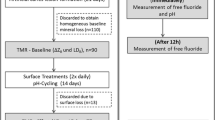

XMT Image analysis

The 3D images from the baseline and treatment scans after 13 days of pH-cycling were aligned using an in-house developed software called ‘Tomview’. These 3D images were then subtracted by running the International Data Line (IDL, Exelis Visual Information Solutions, Boulder, Colorado, USA) software and subsequently mineral loss/gain was detected according to the increase in radiopacity/radiolucency in detected areas (Fig. 1a-d). Randomly selected 45 points of LACs in these detected areas after each ARCL scan were compared with the corresponding 45 points in the baseline scans, and also with the treatment scans after 13 days of pH-cycling [24]. Each line profile was also conducted using ImageJ (U. S. National Institutes of Health, Bethesda, Maryland, USA). A line profile was drawn through the low mineral density to the high mineral density parts. These line profiles were then recorded for the successive scans by clicking on the plugins and macros, then recording the sections. This process was carried out to ensure that the line profile, which was drawn, was exactly in the same position for all the successive scans for that section of each sample. The line profile of all samples in each group was cumulated average to avoid the tooth variation.

Part of a single slice from the re-constructed XMT image of a sample treated by (a) Group (1) Deionised water; (b) Group (2) BG with 540 ppm F; (c) Group (3) 1,450 ppm F; (d) Group (4) 5,000 ppm F; (left) baseline, (middle) after the development of ARCLs, (right) after the application of different treatments with 13 days of pH-cycling

The quantitative mineral density surface measurements (Table 2) demonstrated an increase in mineral contents within the ARCL areas for each toothpaste group after 13 days of pH-cycling. The surface mineral density (mean ± SD) increased for Group 2 (0.11 ± 0.10), Group 3 (0.30 ± 0.07) and Group 4 (0.22 ± 0.10), whilst there was an evidence of decrease in the Group 1 (-0.07 ± 0.10) (p < 0.05).

Line profile of mineral density by XMT

A line profile through all the ARCLs showed evidence of mineral loss compared to the baseline measurements. In addition, after 13 days of pH-cycling, there was an increase in the mineral density on the surface, whilst a decreased mineral density was observed within the subsurface for all groups (Fig. 2).

Line profile plotted between varying mineral density (g cm− 3) and distance(mm) in the root dentine from surface to subsurface. (a) Group (1) Deionised water; (b) Group (2) BG with 540 ppm F; (c) Group (3) 1,450 ppm F; (d) Group (4) 5,000 ppm F; (e) Comparisons at baseline for all groups; (f) Comparisons after ARCLs in all groups; (g) Comparison after pH-cycling in all groups

The mineral density in Group 1 increased 0.14 mm from the surface towards subsurface. There was a decreased in mineral density from 0.26 to 0.5 mm after the pH-cycling (Fig. 2a). In Group 2, the mineral density increased 0.18 mm in depth from the surface to the subsurface after the pH-cycling. However, mineral loss was noticeable between 0.30 and 0.50 mm from surface (Fig. 2b).

In the Group 3, the total mineral density changes from the surface to subsurface was 0.4 mm, and there was an increased in mineral density from 0.12 to 0.28 mm and 0.34 to 0.38 mm from the surface to subsurface after the pH-cycling (Fig. 2c). The loss of minerals also occurred in the deep subsurface from 0.30 to 0.32 mm and 0.38 to 0.5 mm.

Finally, the depth of increased mineral density after pH-cycling was 0.28 mm in the Group 4, whilst the mineral loss was seen between 0.36 and 0.44 mm from surface (Fig. 2d).

The comparison for all groups in the baseline showed that the mineral density differences were not obvious from sound root dentine (Fig. 2e). The ARCLs comparison in all groups was presented an obvious mineral density loss and the mineral density change keep consistent (Fig. 2f). After pH-cycling with toothpastes treatment, the mineral density for Group 2–4 was higher than that in the Group 1 (Fig. 2g).

The change in mineral density was calculated by the quantitative analysis of the line profiles from the surface to subsurface, which are presented in Table 3. The increased mineral density (mean ± SD) from the surface to subsurface was high in the Group 3 (0.12 ± 0.10) and Group 4 (0.13 ± 0.08) when compared to that in the Group 2 (0.10 ± 0.08). The decreased mineral density was similar in the subsurface for Groups 3 and 4 (p < 0.05).